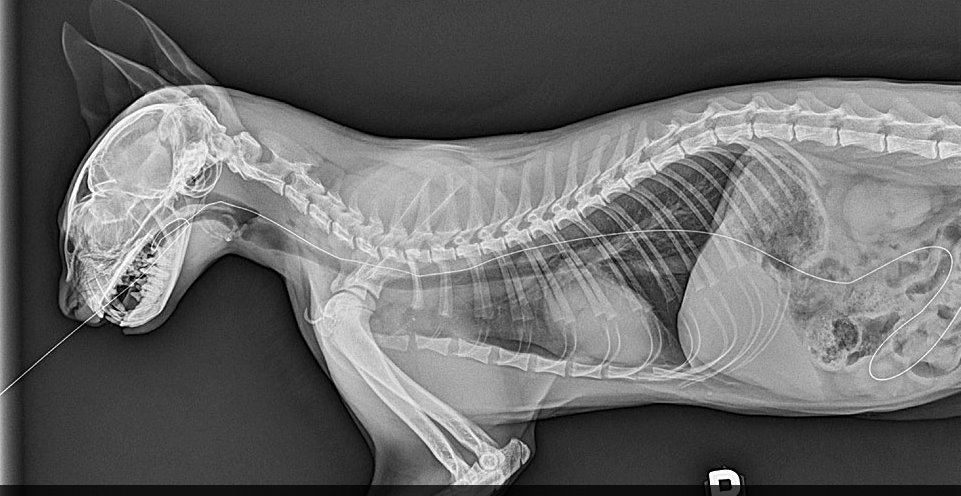

A clínica Bichos e Plantas anuncia aos seus clientes e amigos que está funcionando seu espaço de Ultrassom e Raio X para animais de estimação.

Tais procedimentos são de fundamental importância para o diagnóstico e tratamento eficiente.